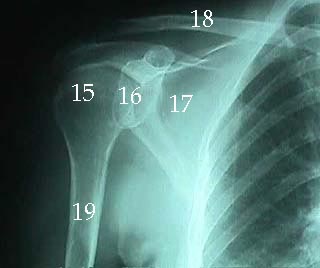

X-Rays

15. Head of Humerus

16. Glenoid Cavity

17. Scapula

18. Clavicle

19 Humerus